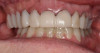

After the restorations were milled, they were sintered and polished for final effect. It was decided that these restorations should not be glazed to avoid the added abrasivity that accompanies this finish to the restoration.22 The patient was then scheduled for temporary crown removal. The final crowns were fitted on the prepared teeth, and the contacts adjusted. The patient reported that she was pleased with the feel and esthetics of the restorations, and the restorations were cemented (Figure 14 through Figure 19).

Fig. 15